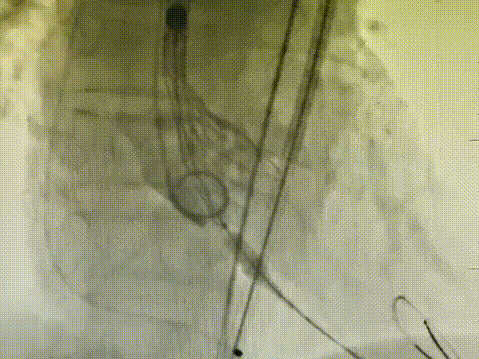

9. 复查造影:瓣膜支架系统膨胀,位置良好,沿导丝将一枚22mm*40mm的VitaFlow®瓣膜球囊扩张导管送至瓣膜支架系统内,定位后扩张瓣膜支架。

手术结果

经猪尾导管复查造影:瓣膜支架系统膨胀良好,未见瓣周漏,冠脉显影正常,食道超声提示瓣膜工作正常,压差解除,无瓣周漏。